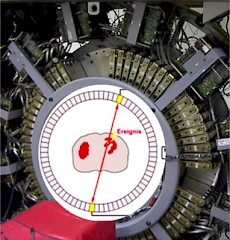

Datenregistrierung PET:

Nur diese zeitgleichen, genau gegenüber liegende Ereignisse werden von einer PET-Kamera mit Hilfe eines Detektorringes registriert.  Der Computer erkennt, dass zwei Ereignisse zusammengehören, wenn sie nahezu zeitgleich gemessen werden.

Der Computer erkennt, dass zwei Ereignisse zusammengehören, wenn sie nahezu zeitgleich gemessen werden.

Solche zwei Werte bezeichnet man als koinzident (zeitgleich). Die Lokalisation erfolgt durch gegenüberliegende in Koinzidenz geschaltete Detektoren.

Die gleichzeitige Detektion der beiden Energieteilchen erlaubt es, die Linie, auf der der Zerfall stattgefunden hat, zu bestimmen. Aus der Überlagerung sehr vieler dieser Linien wird durch Rekonstruktionen die Radionuklidverteilung des Patienten bildlich dargestellt.

Diese paarweise Detektion der Energieteilchen führt zu einer gegenüber anderen nuklearmedizinischen Verfahren etwa 100fach höheren Empfindlichkeit und zu einer erhöhten Ortsauflösung.